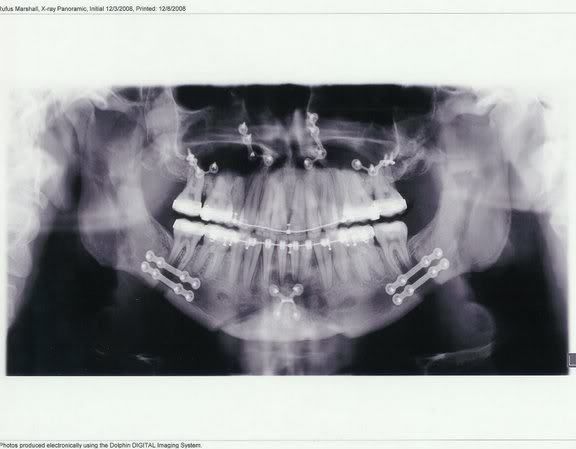

rufus

+1y

Here's a couple of me and my Fiance.

Summer of '08

Post Jaw Surgery - New Year's 2009

Post was last edited on Feb 06, 2009 07:04. Edited 1 time.

91extcab

jaw surgery? who had jaw surgery rufus? you or her?

I did on December 2nd... Its custom, you know.... they C-Notched my chin and added a little length to my top and lower jaw. Check out my Post-Ops